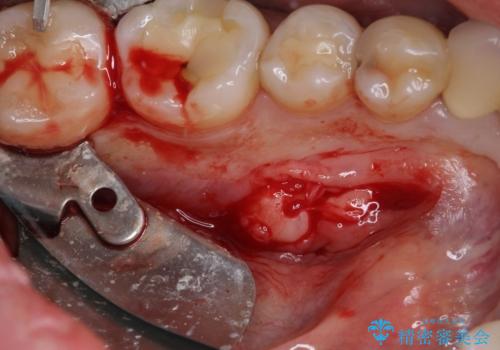

- 張り出している骨隆起による話しにくさを気にして来院された患者様です。

目視でも大きいと分かる骨隆起が認められたため、歯肉を切開した上で切除することとしました。

また、付近の歯に大きなむし歯が認められたため、セラミックインレーによる修復治療も行うこととしました。